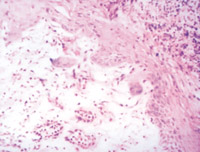

5-2-4 伤后第5天,真皮浅层组织液化性坏死、剥落 HE×100